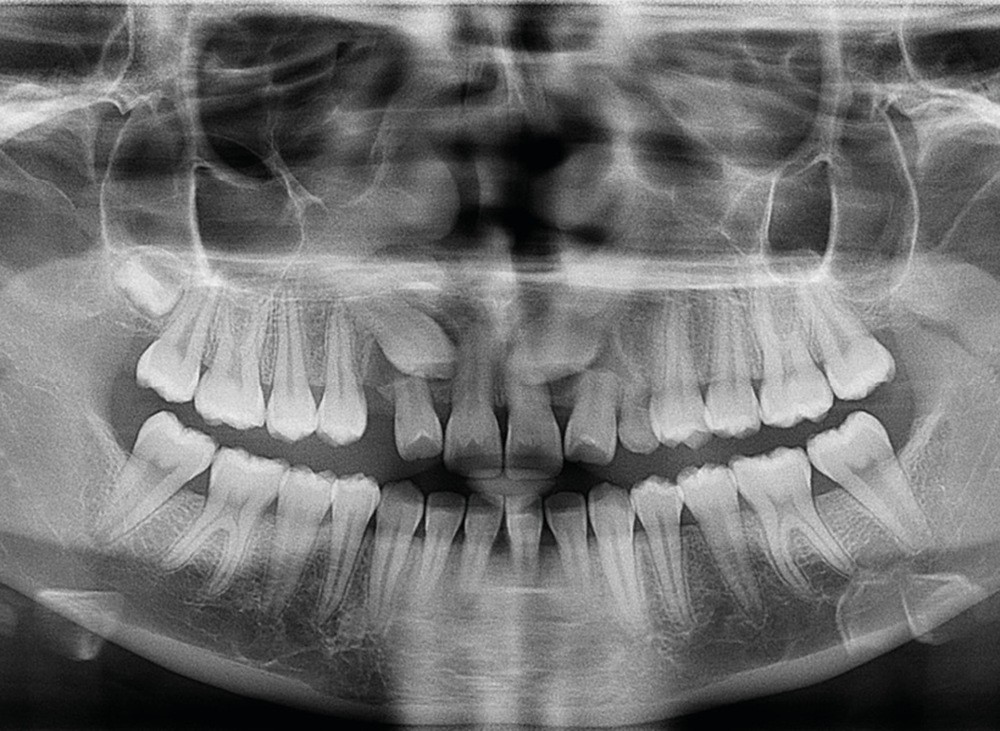

Les examens cliniques et radiologiques ont mis en évidence l’inclusion de 13 et 23, une légère classe II bilatérale par perte d’ancrage, un biotype parodontal de type IV de Maynard et Wilson avec une insertion du frein mandibulaire antérieur papillaire, une biproalvéolie et une typologie hypodivergente. La réalisation d’un examen tridimensionnel a permis de confirmer la localisation palatine de 23 et vestibulaire de 13 ainsi que de visualiser l’étendue des résorptions radiculaires touchant 12, 21 et 22 (fig. 1a-i).

Le plan de traitement choisi comprend les extractions de 63, 12, 22, 34 et 44. Ce choix s’est porté d’une part sur le fait de la présence de résorptions très avancées de 12 et 22 et d’autre part sur la correction de la biproalvéolie facilitée par l’extraction de 34 et 44 qui ont par ailleurs un diamètre légèrement inférieur à 35 et 45.

Les résorptions radiculaires des dents adjacentes aux canines maxillaires incluses sont en effet fréquentes avec un risque plus important chez les femmes. La localisation sagittale de la canine incluse constitue un facteur de risque dans la présence de résorptions radiculaires [3]. Le recours aux examens tridimensionnels est donc indispensable dans le traitement de ces cas.